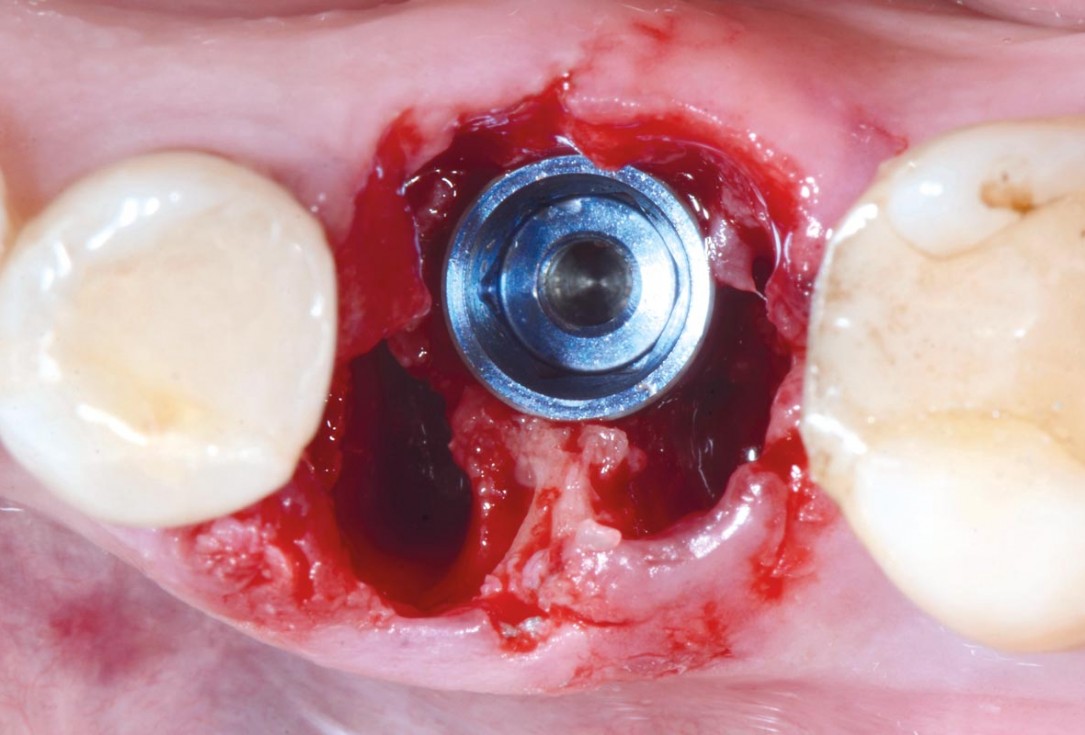

Covering of an immediately placed implant with permamem® - Prof. Z. Mazor

Immediately placed implant covered with permamem®. permamem® passively immobilized by sutures and intentionally left exposed to the oral cavity.